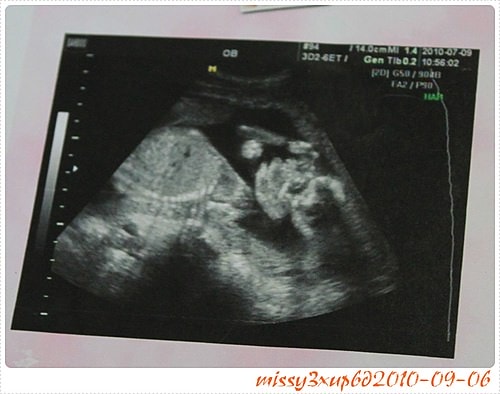

這次去馬偕其實是21W了,我才知道原來例行性超音波,會照的這麼仔細喔? 會看一下手呀,腳呀,肚子頭圍,我其實很囧,因為桓兒根本沒有這樣仔細看過。 這叫做傻傻生傻傻沒事嗎? …

原先已經錯過要預約高層次的我,在收到母血的報告時,真的傻眼了……。 神經管缺陷,紅字。 因為我家掛號本身就很難收到,我是去郵局領,然後心急的領到直接拆開。 …

其實是有些失落的,因為我真的很想知道性別><。 很想趕快知道是女孩,狂喜一下,也很想趕快知道是男孩,好把期盼買女孩衣服的心思放下。 這次去馬偕算是挺早得,至少中午…